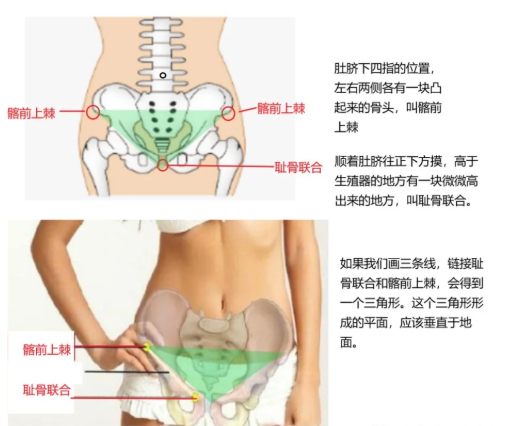

· 骨盆前倾 & 后倾:往往与腰椎过曲 & 过直同时发生,自我评估时可以通过观察腰部的曲度是否过大或过小来判断是否骨盆前倾或后倾。如果要更精确地评估,可以通过观察髂前上棘 (就是用手触摸骨盆最前沿的位置) 和耻骨 联合 (即 会阴 处)是否在一条铅垂线来判断,髂前上棘过于靠前则为骨盆前倾,过于靠后即为骨盆后倾。

测试盆骨的两种方法:方法一:(这个方法更准)

方法二: